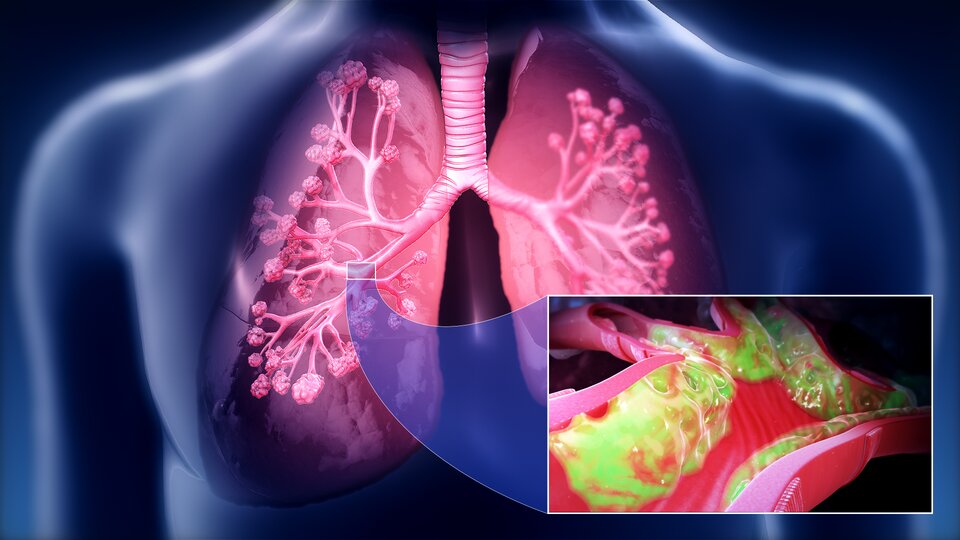

Choroby nowotworowe

Najczęstszą chorobą nowotworową układu oddechowego jest rak płuc. Jego główna przyczyna (odpowiedzialna za ok. 90 proc. przypadków) to palenie papierosów. Ocenia się, że rocznie na świecie umiera z powodu tej choroby ok. 1,6 mln osób. Rozwijający się nowotwór płuc przez długi czas nie daje żadnych objawów lub obserwowane są objawy niespecyficzne (kaszel, chrypa, słabo zaznaczone duszności). Dlatego zazwyczaj choroba diagnozowana jest w zaawansowanych stadiach. Leczenie polega na chirurgicznym usunięciu tkanki nowotworowej oraz wspomagającej radioterapiiradioterapii i chemioterapiichemioterapii.